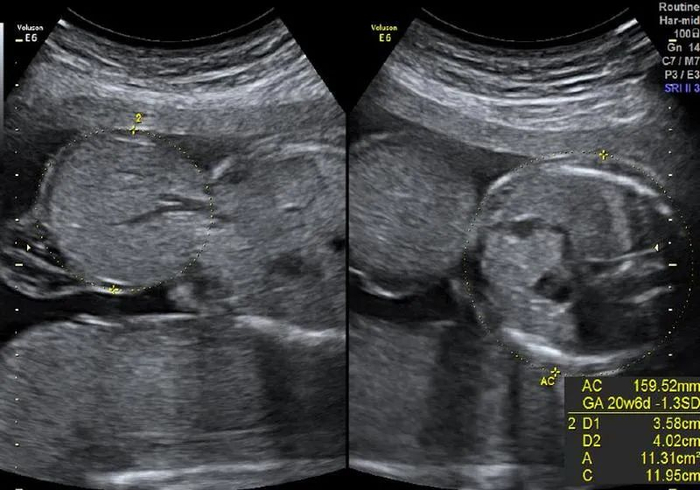

去年9月,黄女士历尽艰辛终于怀孕了。在她憧憬成为母亲的美好未来之时,超声筛查的结果却给了她当头一棒:III级超声检查结果显示,胎儿脐膨出,突出物大小35毫米×36毫米×36毫米

脐带腹部入口处低回声包块,13毫米×12毫米×12毫米,考虑胎儿脐膨出声像。

高羽主任的一番话给了黄女士信心,她选择继续在中山六院产检。孕27周时,超声显示,宝宝其他方面发育良好,但脐膨出的大小已经达到45毫米×46毫米×44毫米(约为成年人拳头大)。